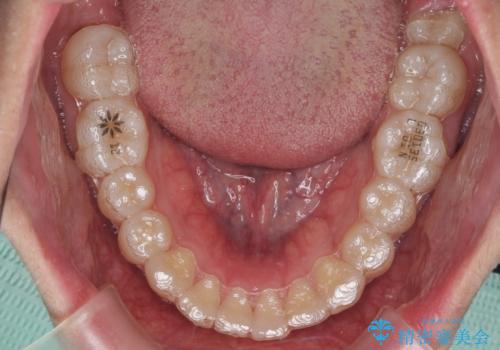

- 矯正装置

- インビザライン

出っ歯の治療 インビザラインで抜歯矯正 親知らずを使用した矯正

- 出っ歯を主訴に来院。

上の小臼歯を2本抜歯しています。

そのかわり、上の親知らずを生かしており、歯の本数は減っていません。

矯正用ミニスクリューを使用しています(インプラント矯正)。

奥歯の歯ならびのずれが大きく、親知らずを抜いてすべて後ろに下げるか、手前の歯を抜いて前歯を下げるかの2択でした。

時間はかかりましたがしっかり前歯を下げて治療しています。